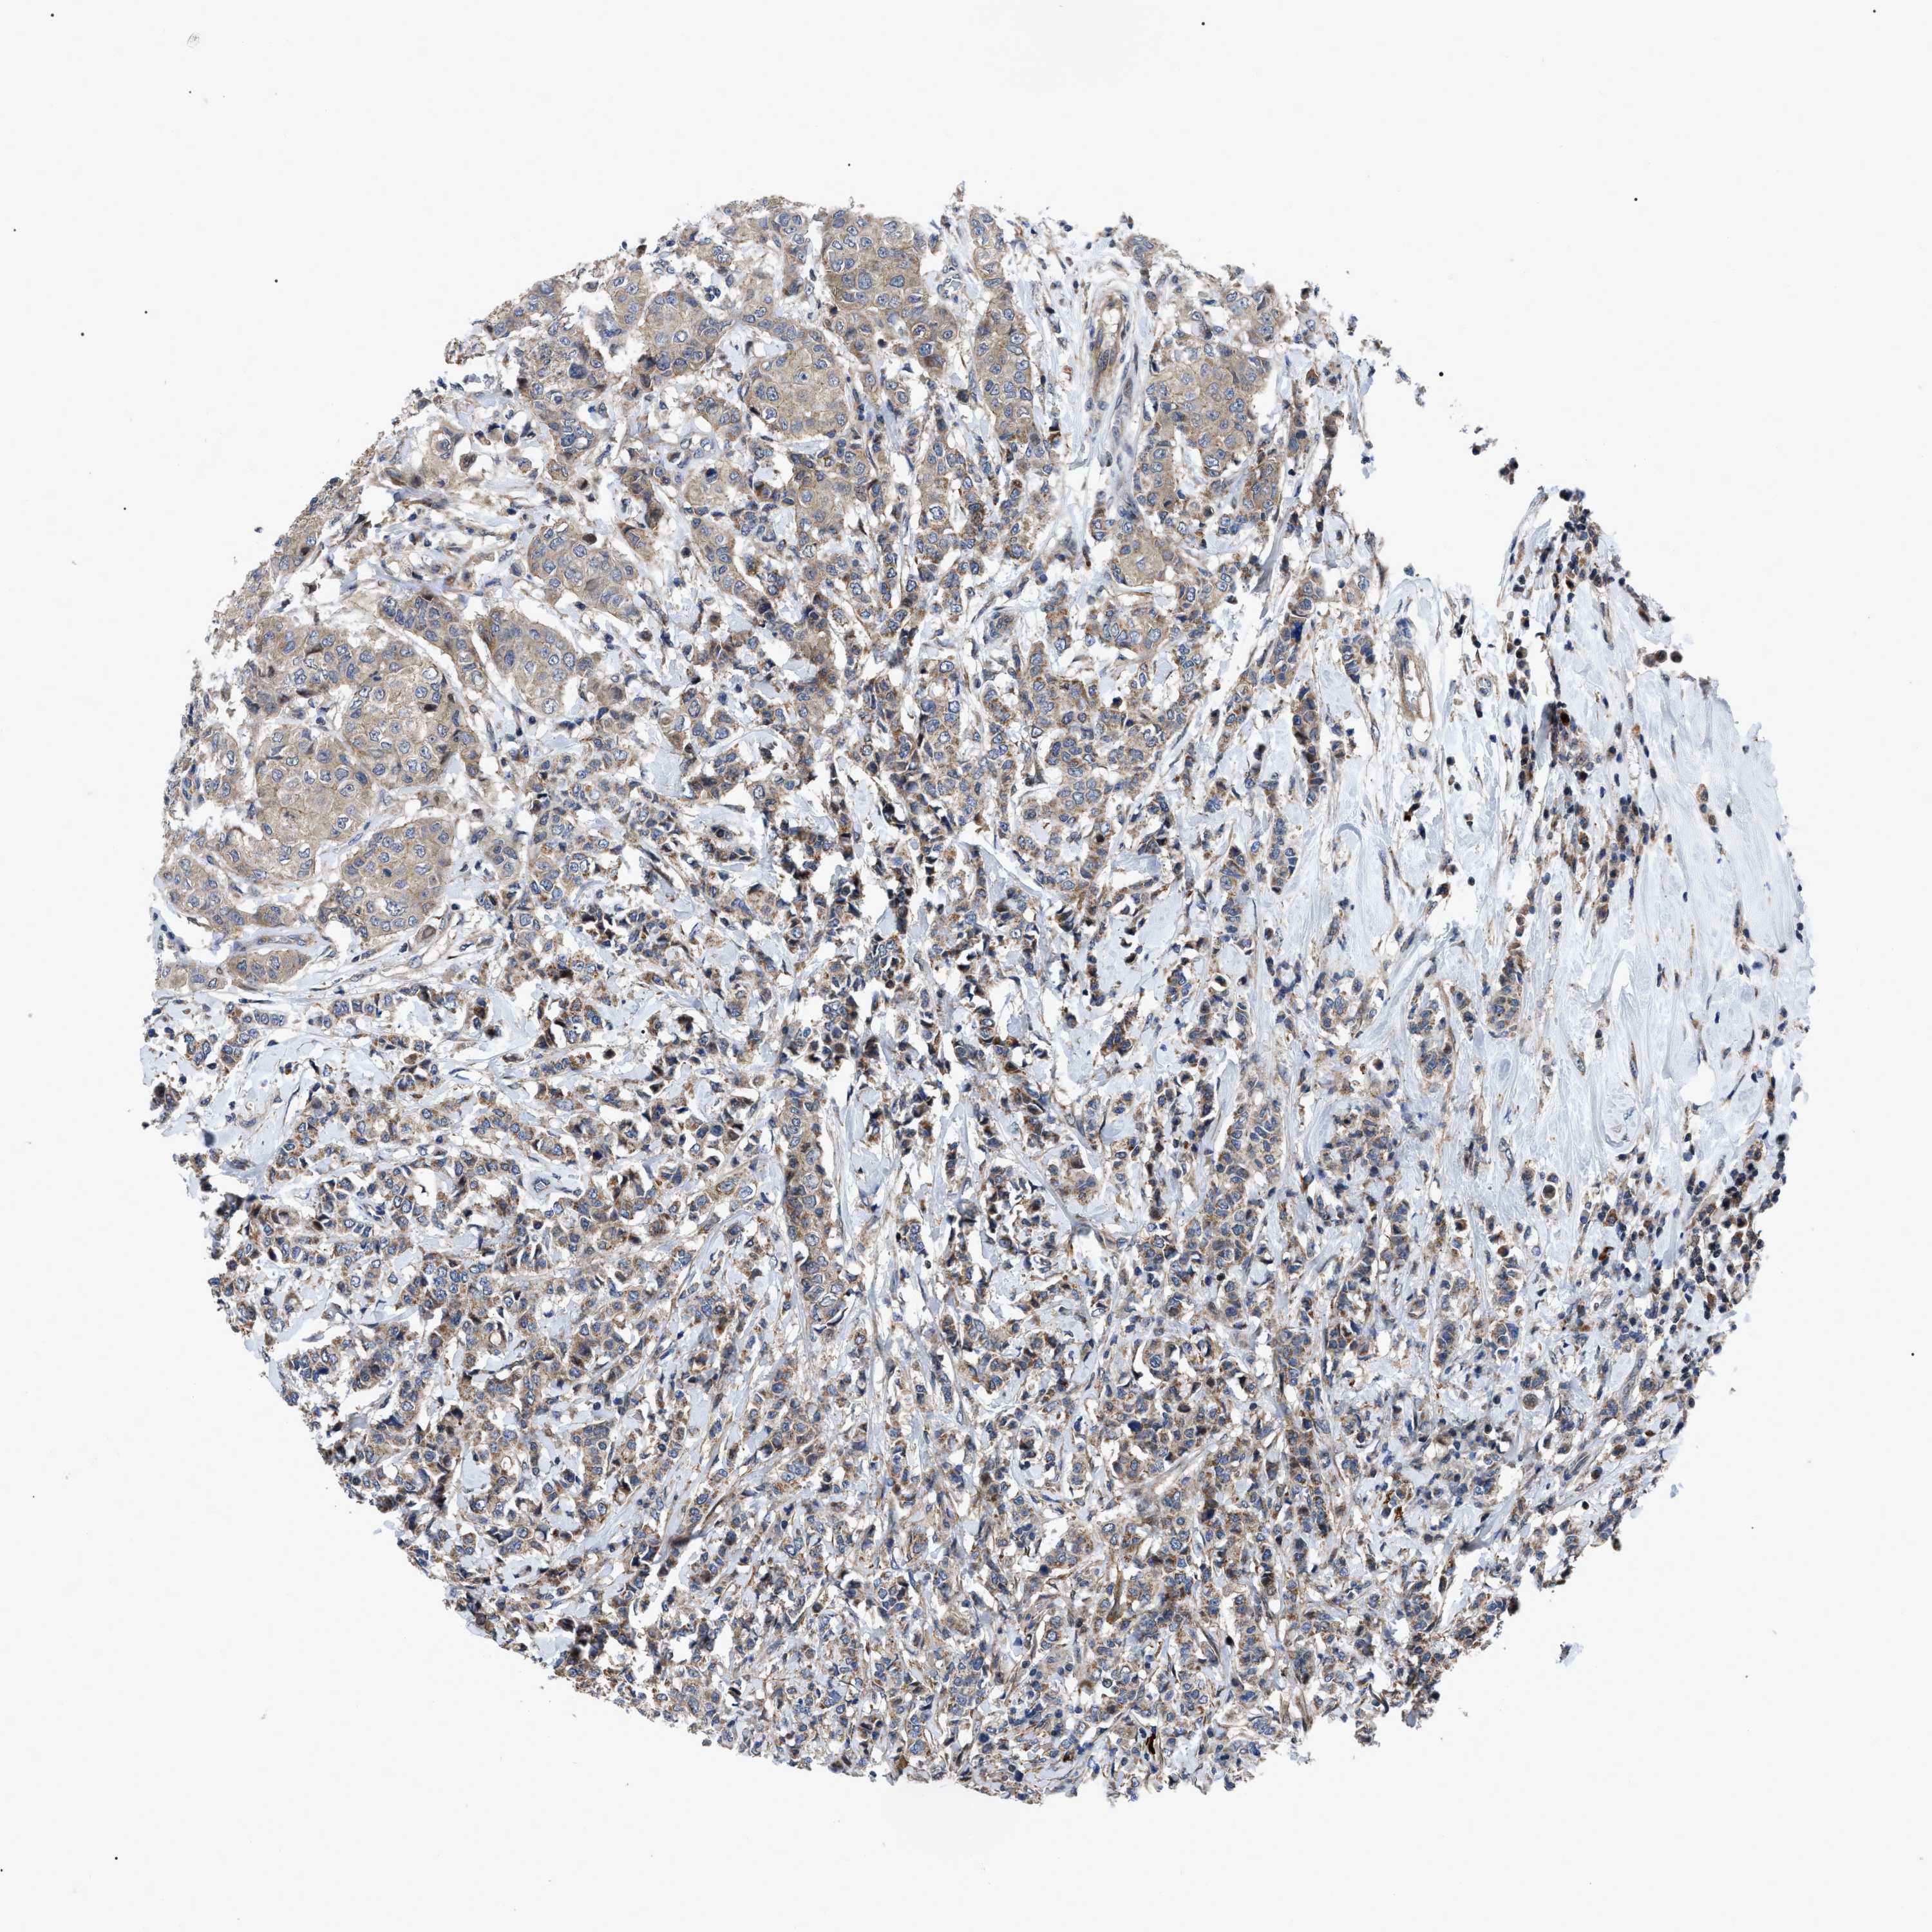

CANCER BREAST CANCER Show tissue menu

BRCA TCGA BRCA VALIDATION PROTEIN EXPRESSION